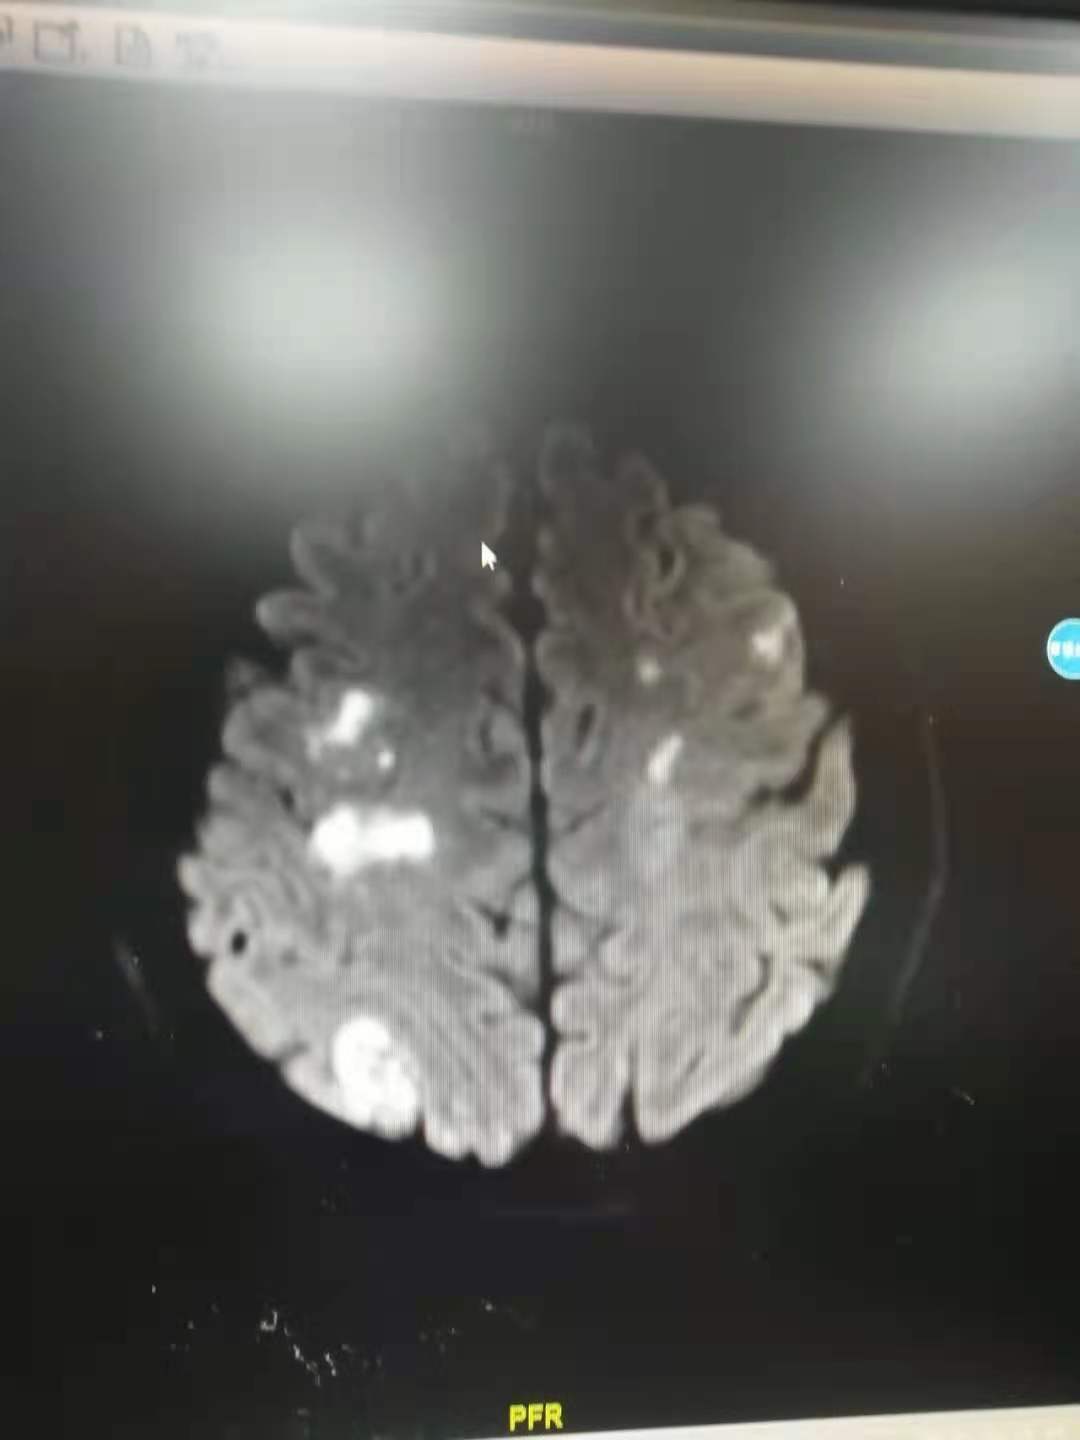

心脏听诊发现杂音,做心脏彩超发现二尖瓣后叶脱垂,二尖瓣瓣叶边缘可见赘生物。ct提示少量脑出血,脑核磁提示多发脑栓塞。结合发热、皮肤损害、化验检查,诊断感染性心内膜炎。

脑MRI提示多发脑栓塞